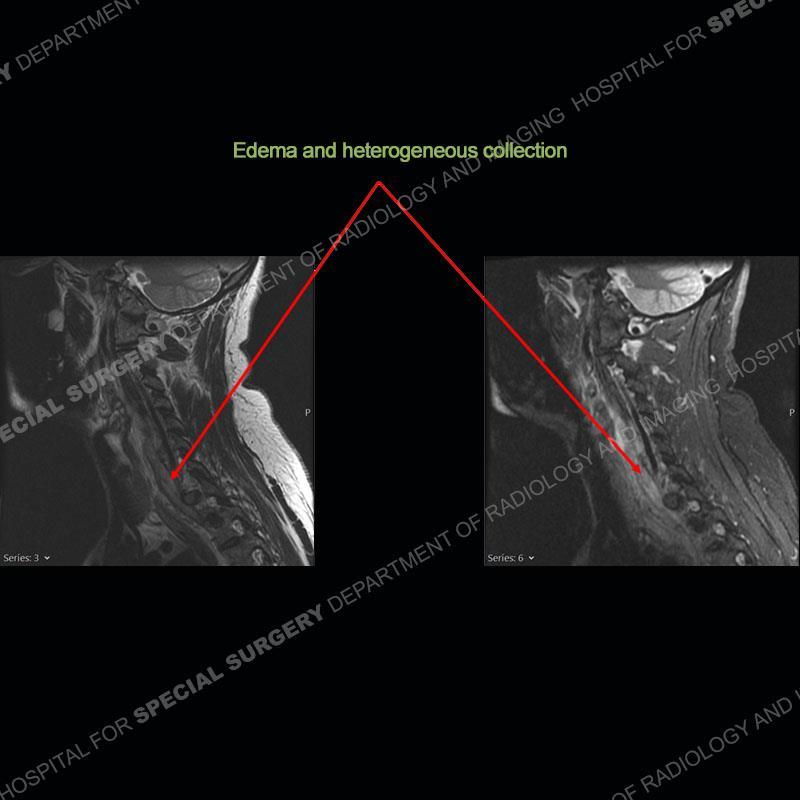

The radiographs demonstrate a prevertebral soft tissue fullness centered at C5-C6 that persists even on extension. There is a slight loss of disc height at C5-C6. The CT more readily shows the prevertebral soft tissue swelling at C5C6 where there is a punctate focus of gas. On the MRI, there is a marked amount of edema and a heterogeneous collection in the prevertebral soft tissue at C5-C6. Edema is present of the C5 and C6 vertebral bodies with a loss of the normal architecture about the disc space. A heterogeneous epidural collection has formed that causes compression of the spinal cord asymmetric to the left side and also precipitates severe left sided neural foraminal stenosis.